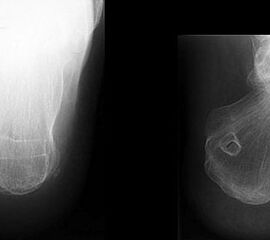

Knöcherne Ausrisse lassen sich in der seitlichen Röntgenaufnahme des Sprunggelenkes ausschließen oder beweisen (Abb. 5). Eine Sonderform bilden hier die Entenschnabelfrakturen des Kalkaneus.

Abbildung 5

Der geübte Untersucher kann anhand des seitlichen Röntgenbildes die Diagnose einer Achillessehnenruptur stellen. Die Konturen des Kager-Dreiecks – gebildet von der ventralen Begrenzung der Achillessehne, der posterioren Tibiakante und der kranialen Kalkaneuskortikalis – verstreichen im Rupturfall (Kager 1939). Die MRT- Diagnostik spielt für die Primärdiagnostik der frischen Achillessehnenruptur eine untergeordnete Rolle und ist im Normalfall nicht notwendig. Anders verhält es sich bei den chronischen Rupturen. Hier ist die MRT ein wichtiges Diagnostikum insbesondere in Hinblick auf die Beurteilung der Sehnen- und Muskeldegeneration (Abb. 6).